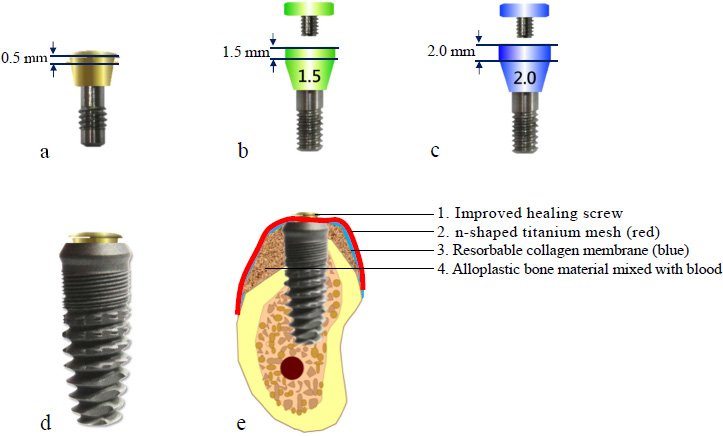

A modified healing abutment was developed to secure a prefabricated titanium mesh on top of the dental implant, ensuring a stable and isolated space beneath the membrane to facilitate osteogenesis in both vertical and horizontal bone defects (Fig. 2a-c).

This modified healing abutment has been granted a patent under the number ZL2017 21817499.0 [17].

- BASIC 4.5×13 mm dental implant system (BASIC omni-tight, USA) (Fig. 2d)

- Bone graft materials 0.5 cc (Bio-Oss, Geistlich, Switzerland) (Fig. 2e)

- Resorbable collagen membrane (Bio-Gide, Geistlich, Switzerland) (Fig. 2e)

- Titanium mesh (ACE Surgical Supply Company, USA, aperture 1 mm, thickness 0.1 mm) (Fig. 2e)

- Modified healing abutment

Design characteristics of modified healing abutments and titanium mesh application. (a) Modified healing abutment with 0.5 mm vertical height, (b) Modified healing abutment demonstrating 1.5 mm vertical dimension, (c) Modified healing abutment with 2.0 mm vertical profile, (d) Clinical application of 0.5 mm healing abutment in conjunction with dental implant, (e) Schematic representation of implant-supported tenting technique utilizing titanium mesh for guided bone regeneration.